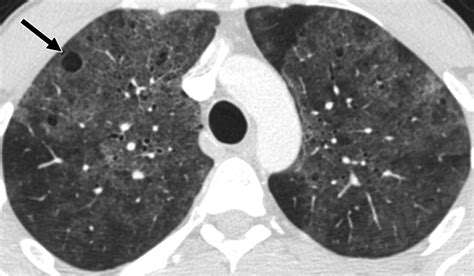

Because blebs in lungs are usually invisible on a standard physical examination, doctors rely heavily on imaging technology to detect them and assess the extent of a pneumothorax if it occurs.

CT Scan (High-Resolution) Provides highly detailed images that can pinpoint the exact location and size of blebs.

• blebs in lungs radiology

• bulla vs bleb radiology

• what is an apical bleb